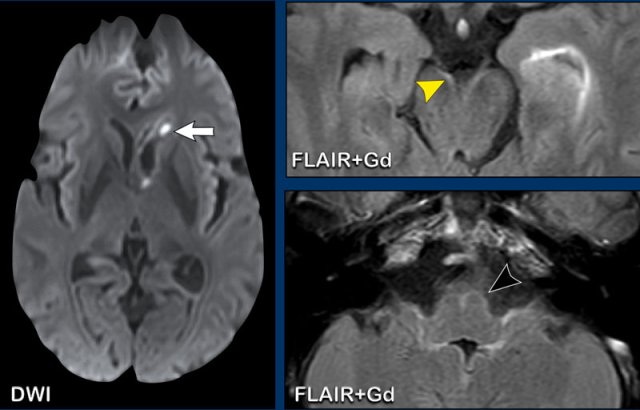

In patients who are treated with intra-arterial thrombectomy, the gyral enhancement can start earlier.

Sometimes it can be difficult.

This patient had a history of breast cancer.

An MRI was done because she had some neurological failure.

On the FLAIR image there is a tiny hyperintense spot (white arrow).

Now this could have been diagnosed as a possible metastasis, but on the T1W-image with Gd there is definitely linear gyral enhancement.

This makes a small subcortical infarction the most likely diagnosis.

A follow up scan (not shown) was performed and definitely excluded the possibility of a metastasis.